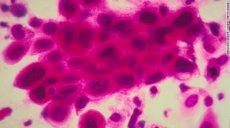

Los cánceres más comúnmente diagnosticados en el mundo son los de pulmón, mama y colon. Las causas más comunes de muertes por cáncer en el mundo son el cáncer de pulmón, hígado y estómago.

En ciertas áreas de África y Asia, el cáncer cervical es la principal causa de muerte en las mujeres. ¿Qué hay detrás de este aumento? El envejecimiento y el crecimiento de la población mundial, así como la propagación de factores de riesgo de cáncer en las naciones de bajos y medianos ingresos. Estos incluyen al consumo de tabaco, la obesidad, la falta de actividad física y una dieta poco nutritiva.